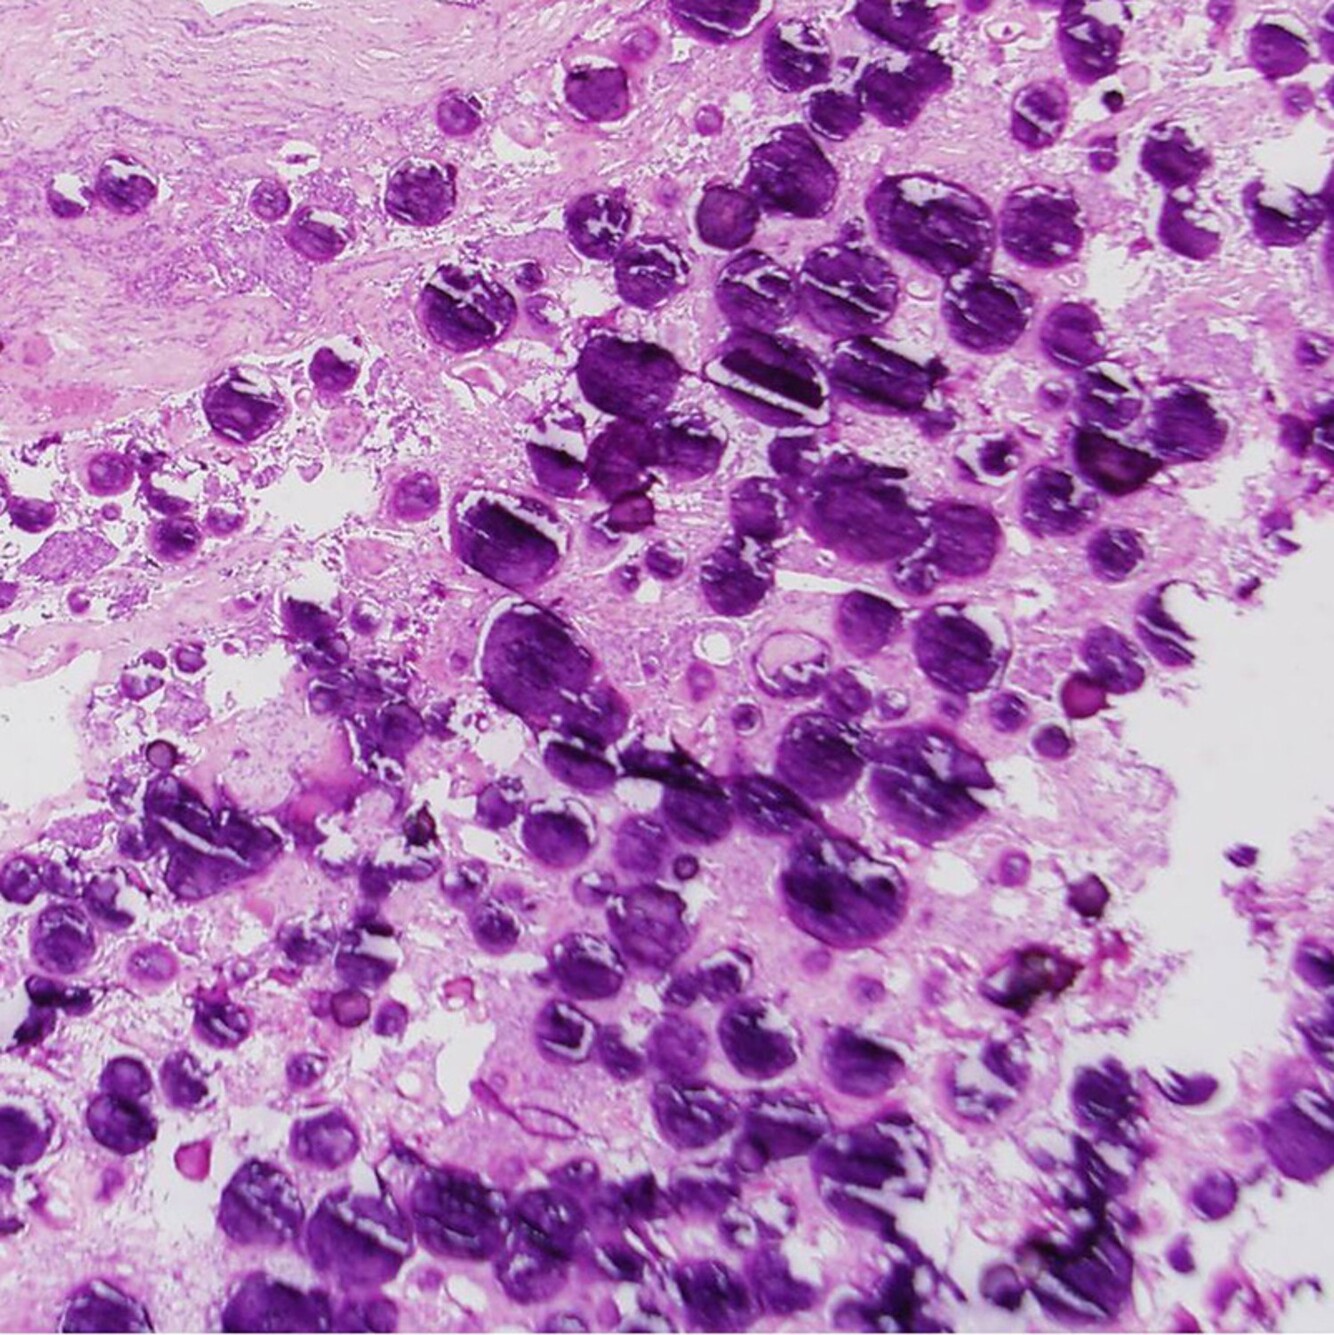

You biopsy a multifocal lesion in the brain of a 60-year-old woman. The final pathology slide is shown below. What is the primary method of initial treatment for this neoplasm?

This slide demonstrates a cellular proliferation around small vascular channels/arterioles. This is highly suggestive of CNS lymphoma, and initial treatment can be carried out with steroids.